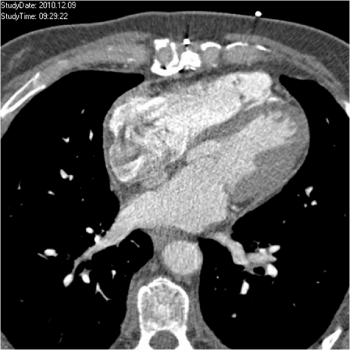

Figure 5b: Cardiac CT at follow-up; 4-chamber view.